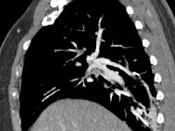

问题 男,56岁,食管癌术后,胸痛,呼吸困难,结合CT图像,最可能的诊断是 ( )

选项 A.食管癌肺转移 B.肺栓塞 C.支气管扩张 D.肺水肿 E.肺不张

答案 B